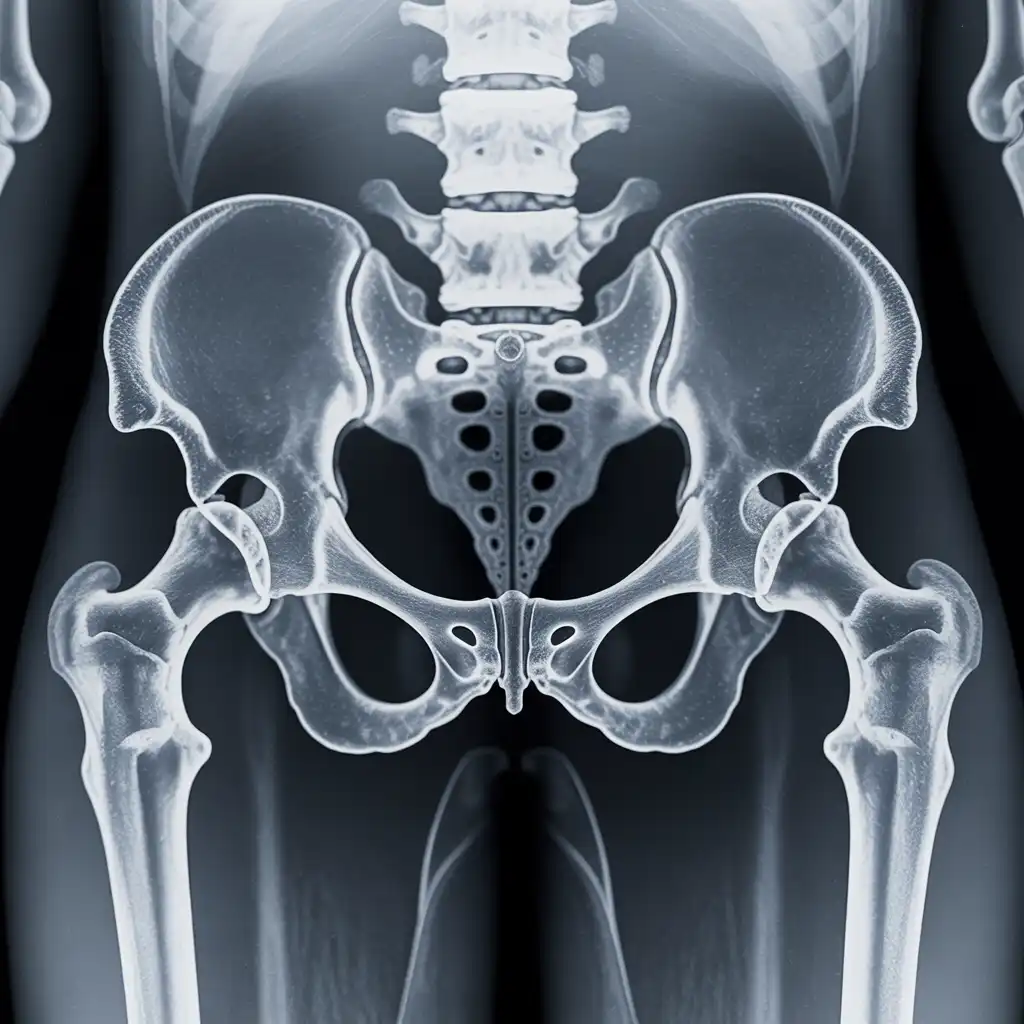

Una lastra a domicilio è una radiografia eseguita direttamente a casa del paziente, grazie all’intervento di un tecnico sanitario qualificato dotato di apparecchiatura digitale portatile.

L’esame viene effettuato sul posto, senza necessità di spostare la persona dal letto o dalla poltrona, e garantisce una qualità diagnostica paragonabile a quella di un reparto ospedaliero.

Nel corso degli anni abbiamo effettuato migliaia di radiografie a domicilio in abitazioni private, RSA, centri di assistenza e strutture per anziani, utilizzando apparecchi digitali portatili certificati che garantiscono immagini precise e tempi di esecuzione rapidi.